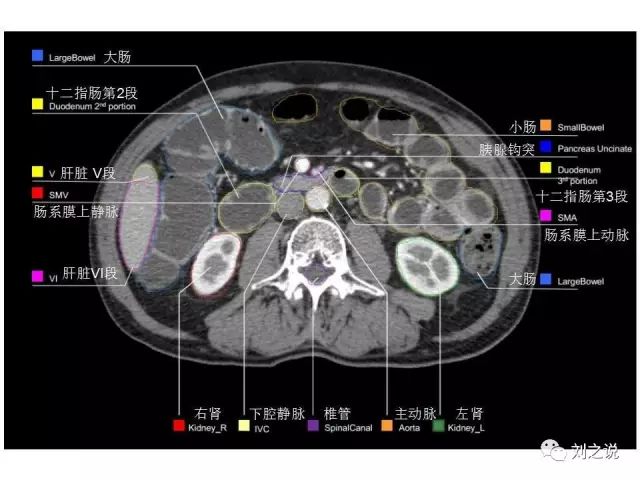

参考RTOG共识和3D-body解剖。

来源:刘之说